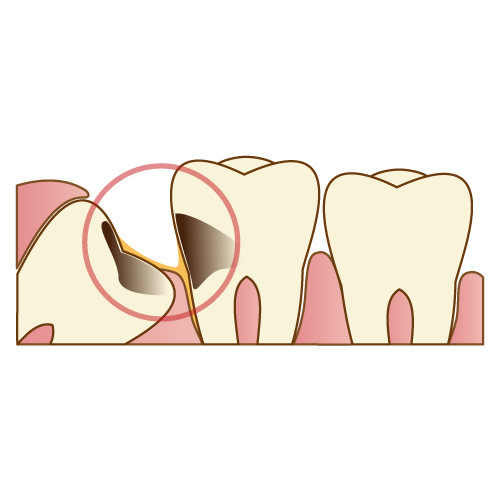

親知らず付近は歯ブラシが普段から物理的に届かなくなってしまっているケースが多く、十分な歯磨きが困難な事が多いことから虫歯好発部位となります。

汚れの管理ができない事から大きな虫歯ができてしまい、虫歯が親知らずの中の神経まで到達し、神経を興奮させる事により痛みが出てしまいます。

このようなケースは親知らずをすぐに抜歯しないと痛みが治まらないため、速やかに抜歯をしたいところですが、自発痛があり夜眠れないほどにズキズキしてしまっている場合はやはり急性炎症の状態ですので、一度鎮痛薬や抗菌薬で神経の興奮を抑えてあげなければ抜歯をするための麻酔が効かない事もあります。

この絵のように一つ前の歯までも大きくむし歯になってしまっているケースも多いです。このぐらいの深さですと、前方の歯の神経を取る処置をしないと痛みが治まらない事も多いです。